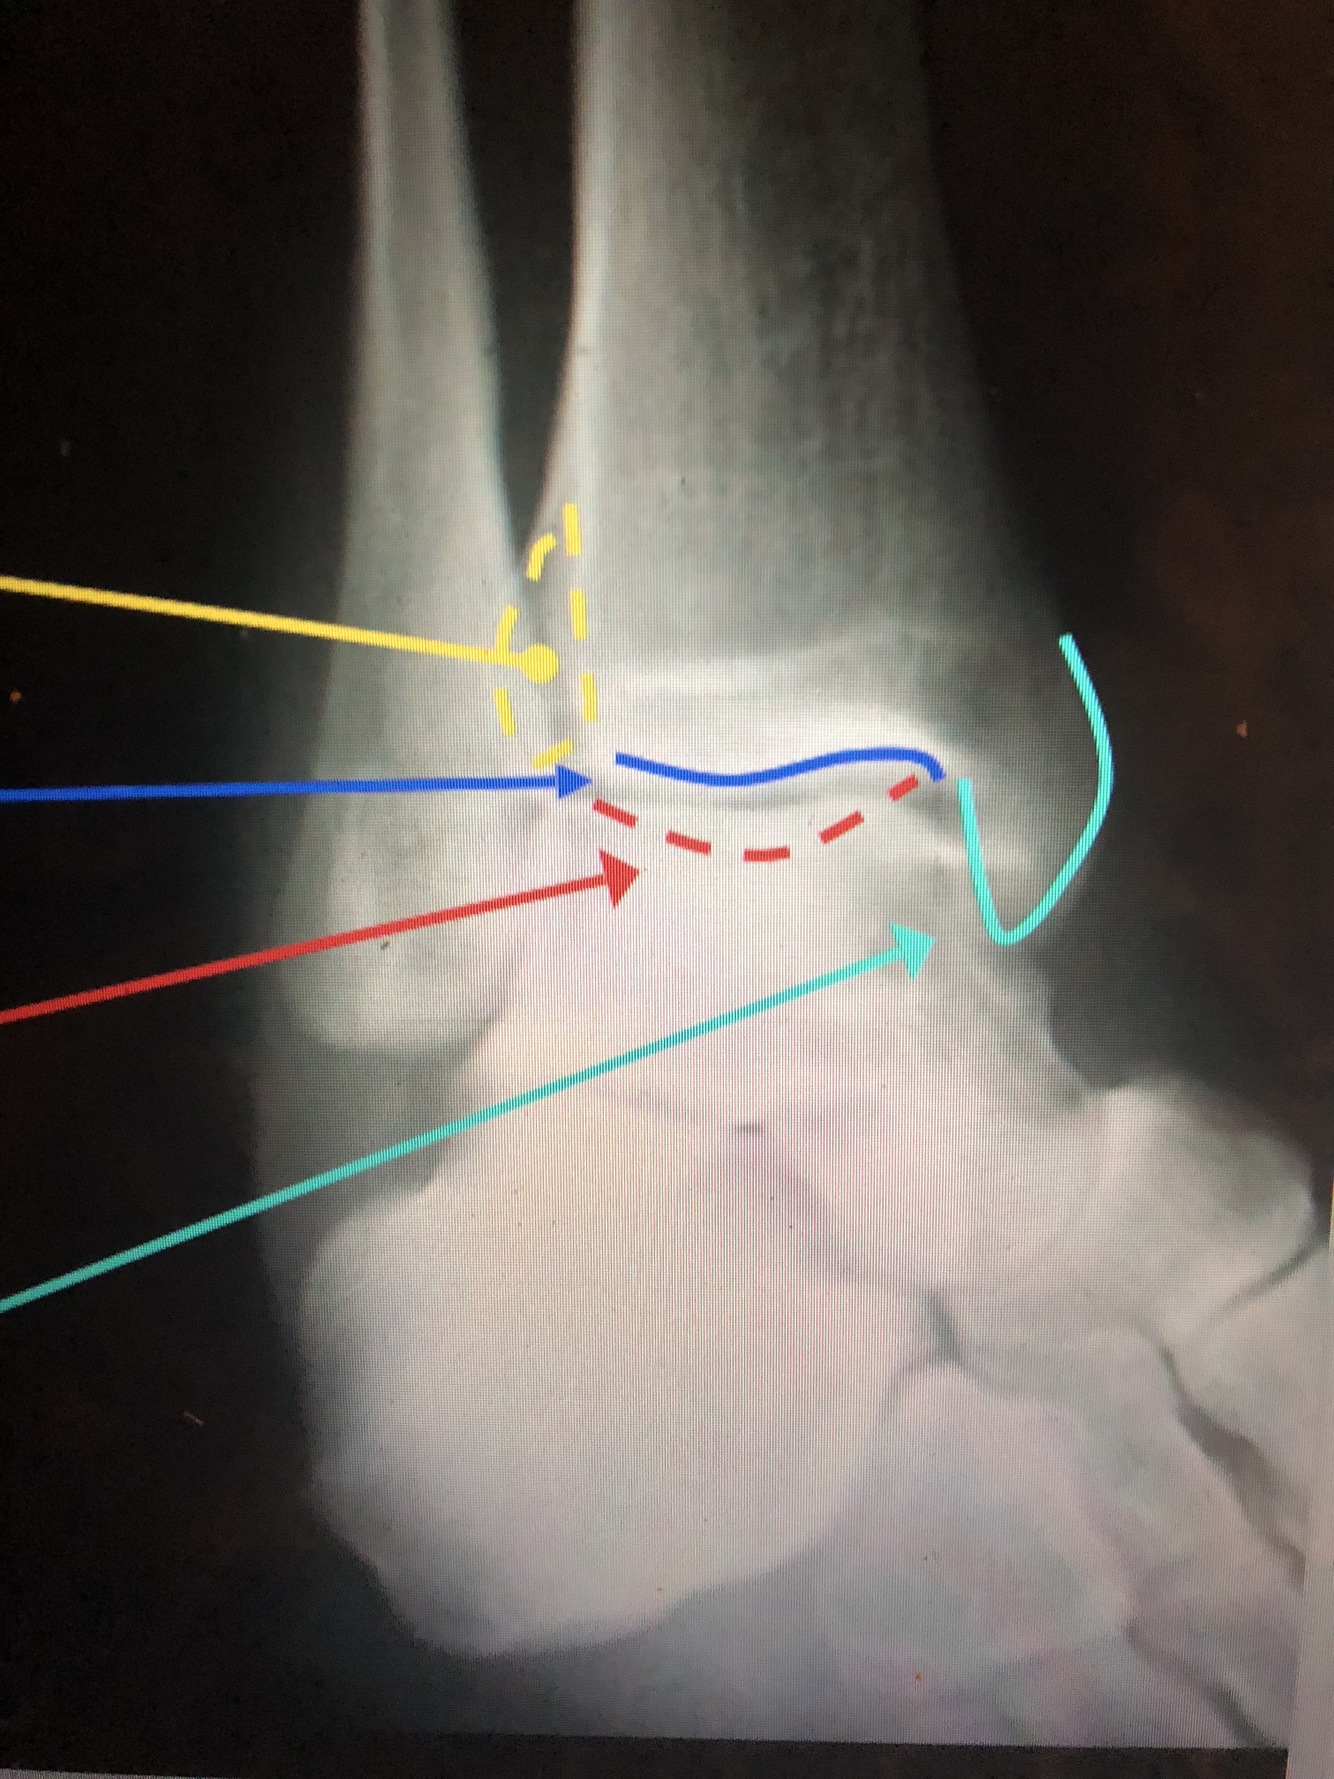

What is the yellow dotted line?

Fibular Notch

What is the dark blue line?

Plafond

What is the red line?

Posterior Malleolus

What is the light blue line?

Medial Malleolus

What is the blue line?

Lateral Malleolus